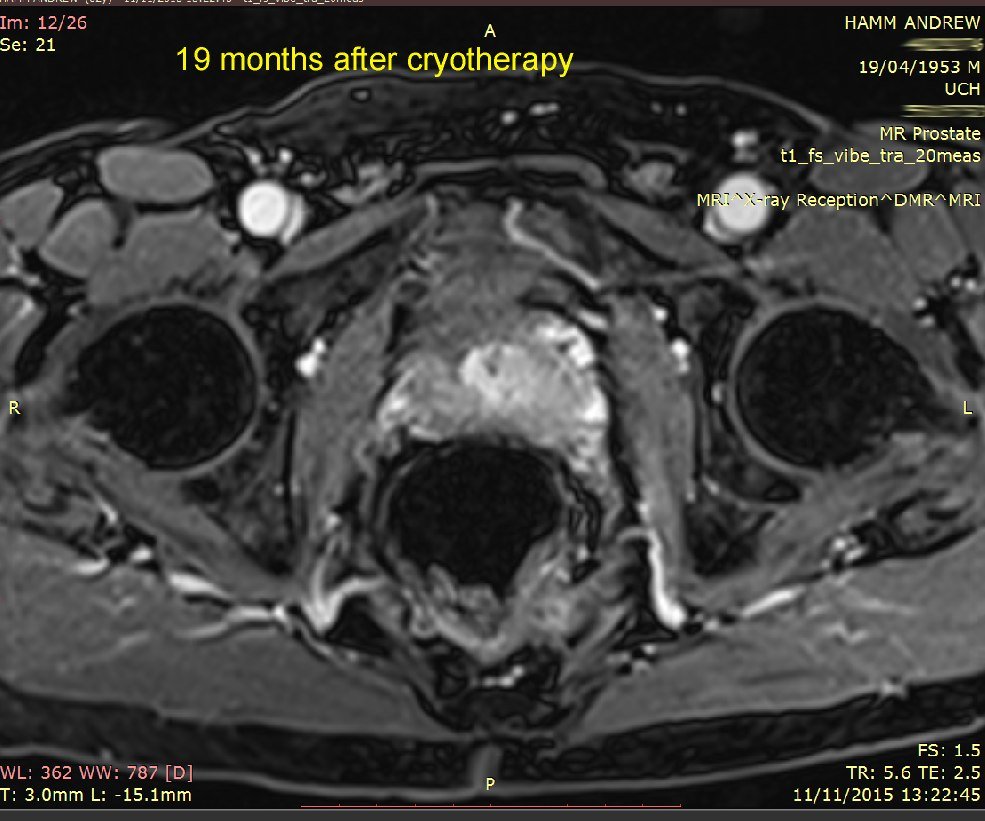

I've put 3 MRI images taken in November 2015. Compare these with my earlier ones below that, from 24 November 2014. Whilst not commenting specifically on these, the consultant said that the overall MRI had not revealed any significant (observable) prostate cancer.

The image below shows the cryo ablated (destroyed) area-

the

dark area. The

surgeon says "it looks very good", so I presume that means he ablated an ideal area.

(Remember: "left" in the image is the right hand side of my body)

I must say, the area ablated looks

much larger than the red area marked on my

first MRI. However, the surgeon did say that he would target an area a little larger than that, to be sure all the index lesion was killed off, plus I guess the precision of the cryo comes into play.